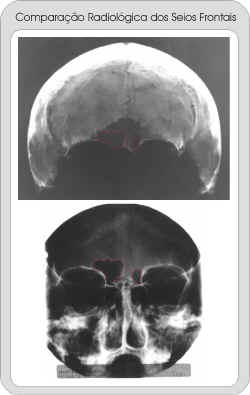

IdentificaÓÐo Humana por ComparaÓÐo Computadorizada de Imagens

RadiogrÃficas dos Seios Frontais